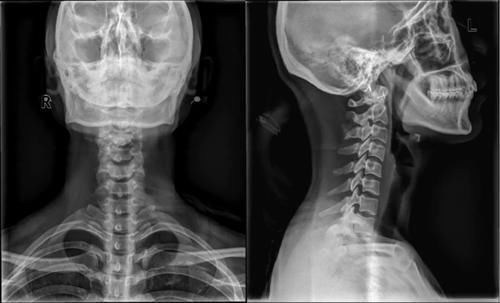

Case11:F,5y;颈部疼痛3天。

文章插图